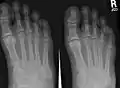

The metatarsal bones, or metatarsus (pl.: metatarsi), are a group of five long bones in the midfoot, located between the tarsal bones (which forms the heel and the ankle) and the phalanges (toes). Lacking individual names, the metatarsal bones are numbered from the medial side (the side of the great toe): the first, second, third, fourth, and fifth metatarsal (often depicted with Roman numerals). The metatarsals are analogous to the metacarpal bones of the hand. The lengths of the metatarsal bones in humans are, in descending order, second, third, fourth, fifth, and first.[1] A bovine hind leg has two metatarsals.[2]

Fracture of the base of the 5th metatarsal